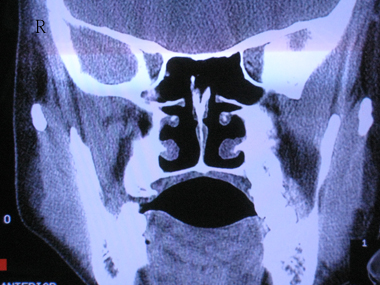

以下是引用zhangzhongshou在2007-5-26 23:02:00的发言:[br]左侧上颌窦霉菌感染,右侧慢性上颌窦炎(粘膜肥厚为主)。